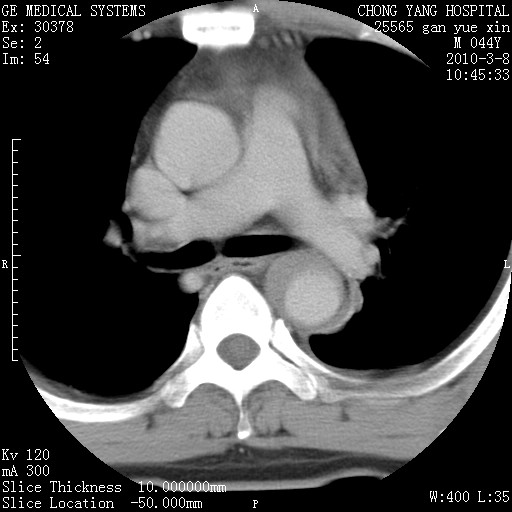

标题: CT24940:主动脉增强,典型病例。 [打印本页]

标题: CT24940:主动脉增强,典型病例。

夹层动脉瘤。

夹层动脉瘤,典型

主动脉夹层。

动脉夹层的分型:

⒈debakey分型:根据主动脉夹层累及部位,分为三型:ⅰ型:原发破口位于升主动脉或主动脉弓部,夹层累及升主动脉、主动脉弓部、胸主动脉、腹主动脉大部或全部,少数可累及髂动脉。ⅱ型:原发破口位于升主动脉,夹层累及升主动脉,少数可累及部分主动脉弓。ⅲ型:原发破口位于左锁骨下动脉开口远端,根据夹层累及范围又分为ⅲa,ⅲb。ⅲa型:夹层累及胸主动脉。ⅲb型:夹层累及升主动脉、腹主动脉大部或全部。少数可累及髂动脉。

⒉stanford分型:a型:夹层累及升主动脉,无论远端范围如何。b型:夹层累及左锁骨下动脉开口以远的降主动脉。

夹层动脉瘤,少量胸水

夹层动脉瘤;左侧少量胸腔积液。